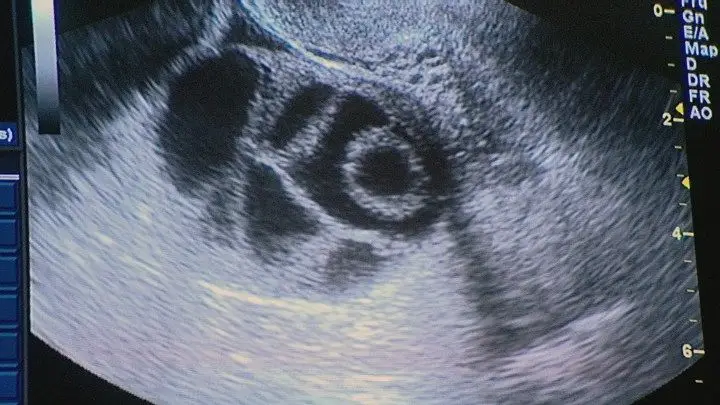

Dentro de duas semanas vai ser decidido o primeiro caso em Portugal de barriga de aluguer. Trata-se de uma avó que se propõe a gestar o neto, porque a filha não tem útero. Foram já definidos não só os limites de idade para os casais que podem beneficiar do processo mas também outras regras para os envolvidos.